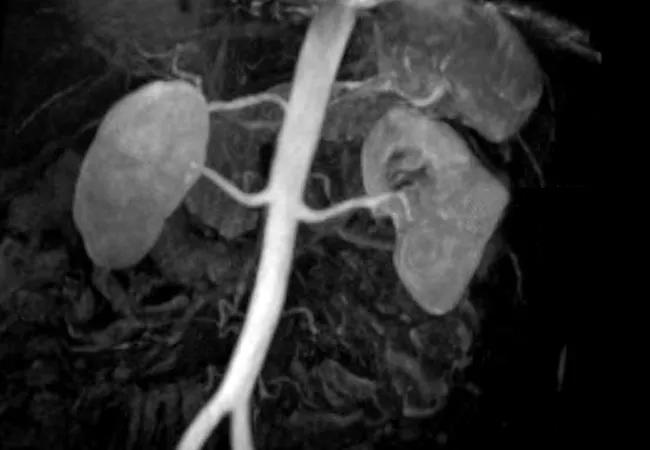

650×450-3D-MR-kindey